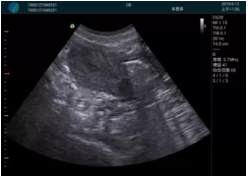

清晰顯示孕囊,通過軟件包計算孕齡7w+6d

M20實(shí)時引導(dǎo),術(shù)中清晰顯示孕囊被破壞和抽吸針的過程,清晰顯示吸引針

抽吸結(jié)束后縱切子宮,孕囊已被完全抽吸,未見明顯殘留

橫切子宮,發(fā)現(xiàn)右側(cè)宮腔靠近宮角處有少許脫模樣殘留

M20引導(dǎo)下,抽吸針找到右側(cè)宮角處再次清掃

二次抽吸后再次進(jìn)行超聲檢查,宮腔未見殘留,宮腔線清晰顯示